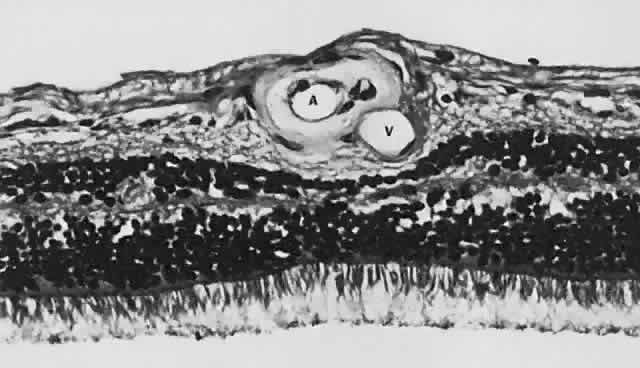

and has sharp borders (Fig. 13).  Fig. 11. A. Section of retina with hemorrhage in the nerve fiber layer (between the two large arrows). Notice that the limits of the hemorrhage are not clearly defined, since

scattered red blood cells can be seen to the right of the right-hand

large arrow. This histologic picture corresponds to a clinically observed

fame-shaped hemorrhage with an indistinct border. The detached

posterior hyaloid is marked by four small arrows. B. Fundus photograph of nerve fiber layer hemorrhage. They are oriented parallel

to the plane of the internal limiting membrane. Because of their

dispersal within the ganglion cell layer, the borders are “feathery” (flame

shaped). Fig. 11. A. Section of retina with hemorrhage in the nerve fiber layer (between the two large arrows). Notice that the limits of the hemorrhage are not clearly defined, since

scattered red blood cells can be seen to the right of the right-hand

large arrow. This histologic picture corresponds to a clinically observed

fame-shaped hemorrhage with an indistinct border. The detached

posterior hyaloid is marked by four small arrows. B. Fundus photograph of nerve fiber layer hemorrhage. They are oriented parallel

to the plane of the internal limiting membrane. Because of their

dispersal within the ganglion cell layer, the borders are “feathery” (flame

shaped).